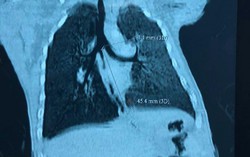

Phòng & chữa bệnh 14:09 29/07/2018Bé gái 2 tháng tuổi ngụ tại Gia Lai bị rò khí quản vào đường mật rất hiếm gặp đã được các bác sĩ chẩn đoán, điều trị thành công.